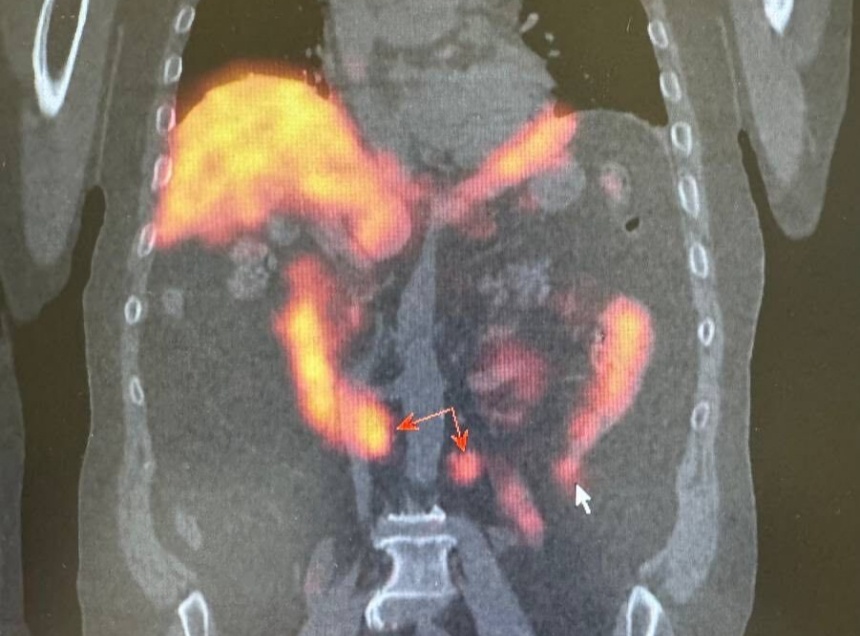

Для получения детальной информации о состоянии лимфатических узлов назначили радионуклидная диагностика. Она позволила определить наличие злокачественного опухолевого процесса в предстательной железе и подтвердить метастатическое поражение ранее выявленных лимфатических узлов к грудной клетке.

Помимо этого, исследование показало активное накопление технеции ПСМА в парааортальных лимфатических узлах с обеих сторон. «При этом, важно отметить, что на компьютерной томографии не было явных структурных изменений, что затрудняло оценку их состояния и возможности метастазирования», – обратили внимание в пресс-службе министерства здравоохранения Псковской области.